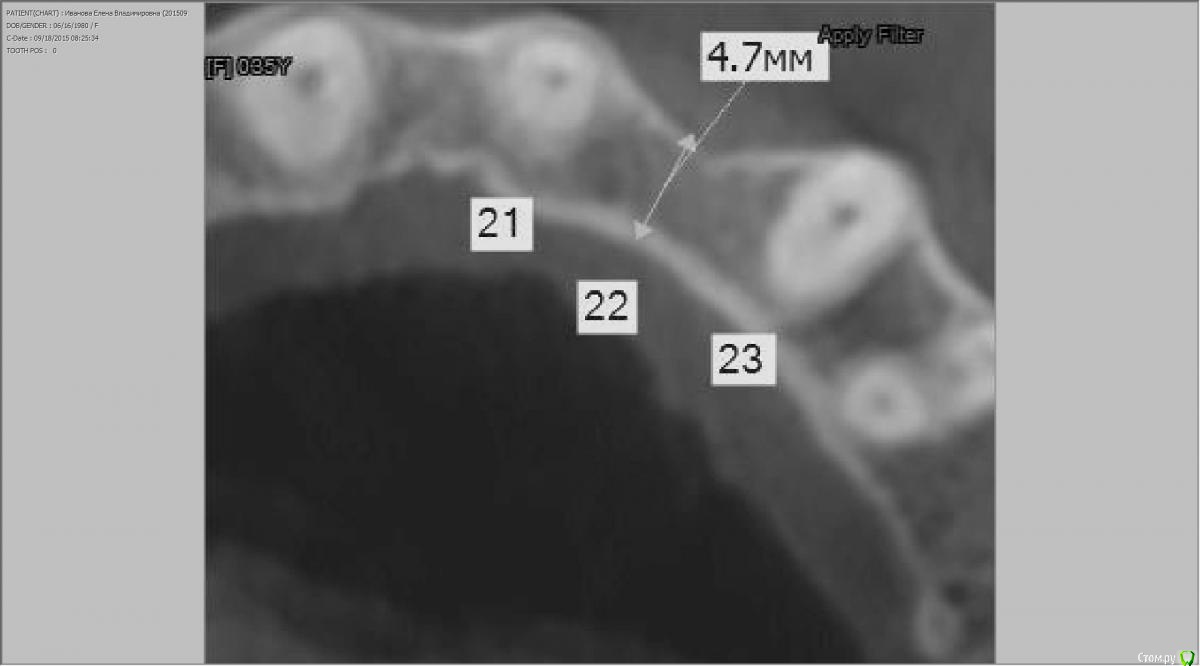

dsfksdkf Опубликовано 25 октября, 2015 Автор Поделиться Опубликовано 25 октября, 2015 (изменено) Недостаточно данных, нужен вертикальный срез кт в этой области, но скорей всего можно сделать надёжно и красиво только пересадкой десны. Будет намного проще и быстрее.то есть без наращивания кости? а куда поместить имплант , на десну? срез прилагаю Изменено 25 октября, 2015 пользователем dsfksdkf Ссылка на комментарий

carloss Опубликовано 25 октября, 2015 Поделиться Опубликовано 25 октября, 2015 На десну тоже можно( шучу), но под и в кость будет красивее. Да, судя по срезу кт в вашем случае точно можно обойтись пересадкой десны. Только это не совсем классическая имплантация, нужно бережно с костью, чтобы она потом не рассасывалась. Боюсь что не многие имплатологи на сегодня пойдут по такому пути.Удачи! Ссылка на комментарий